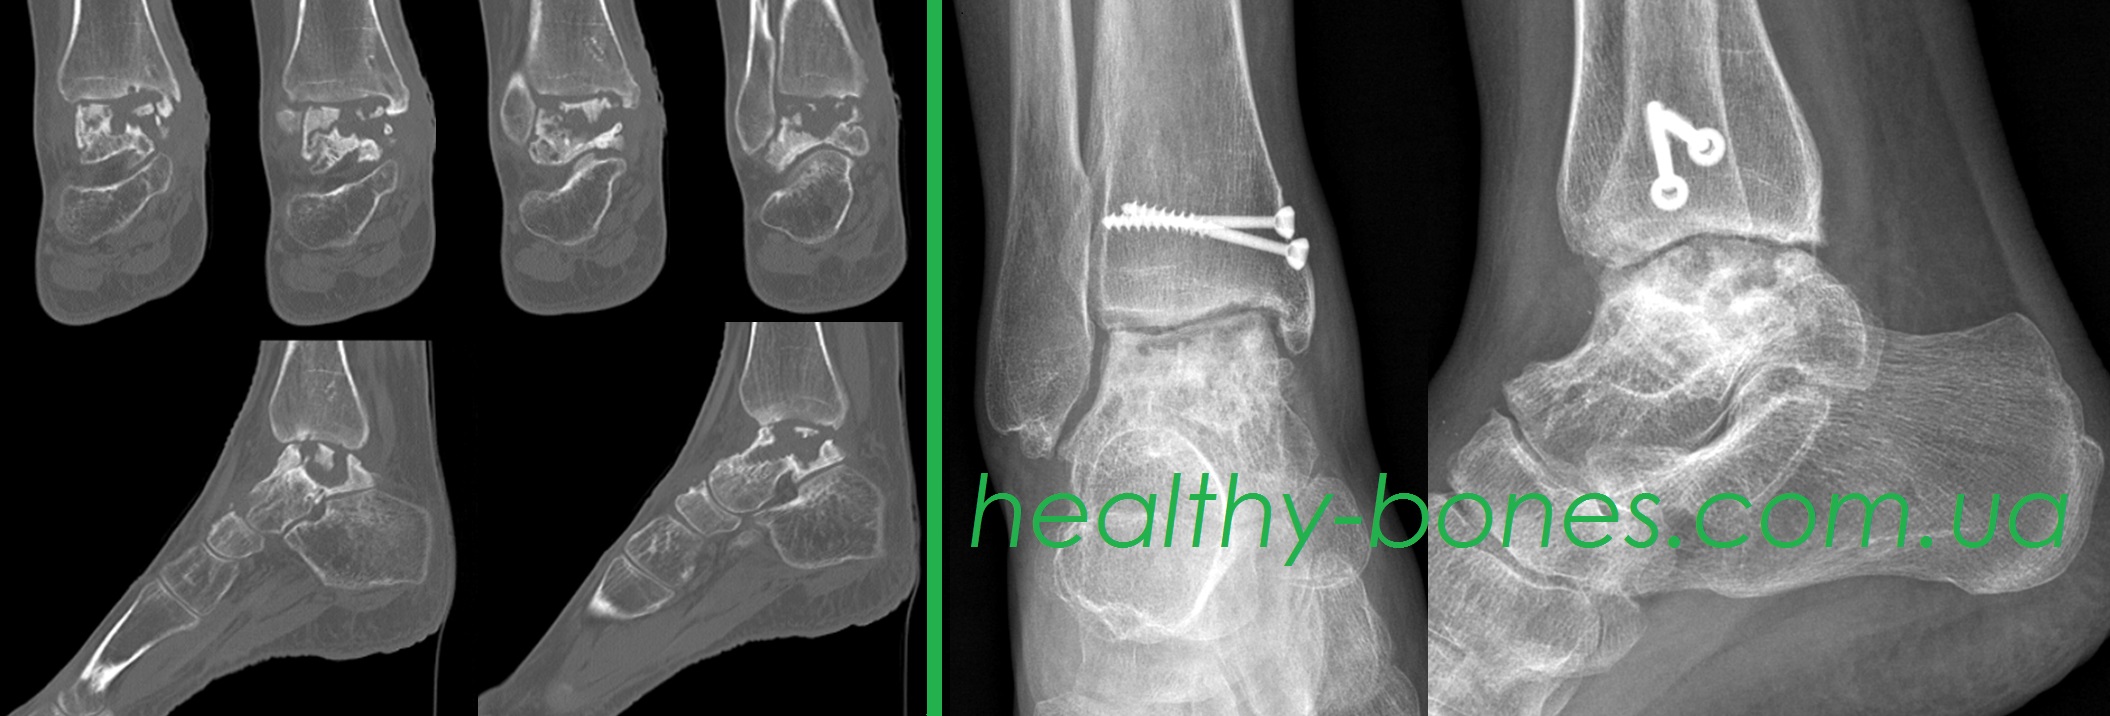

Жінка звернулася до нас з приводу аваскулярного некрозу правої таранної кістки. У 2018 році отримала осколковий перелом правої таранної кістки. У Київському інституті травматології пацієнтці було виконано остеосинтез перелому. Після операції зберігалися сильні болі в області гомілковостопного суглоба. Через 8 місяців після операції у неї був діагностований аваскулярний некроз таранної кістки і запропоновано виконати артродез гомілковостопного суглоба. Пацієнтка консультувалася в клініках Бельгії, Австрії, Німеччини та США і у всіх клініках їй пропонували виконати артродез суглоба або поставити штучний суглоб і говорили про те, що нормально вона ходити вже не зможе.

При обстеженні у пацієнтки був виявлений тотальний некроз блоку таранної кістки і відсутність хрящової тканини. Пацієнтці було запропоновано розроблене нами етапне оперативне лікування з васкуляризацією таранної кістки і використанням стовбурових клітин. Лікування було розпочато практично через рік після виявлення аваскулярного некрозу кістки.